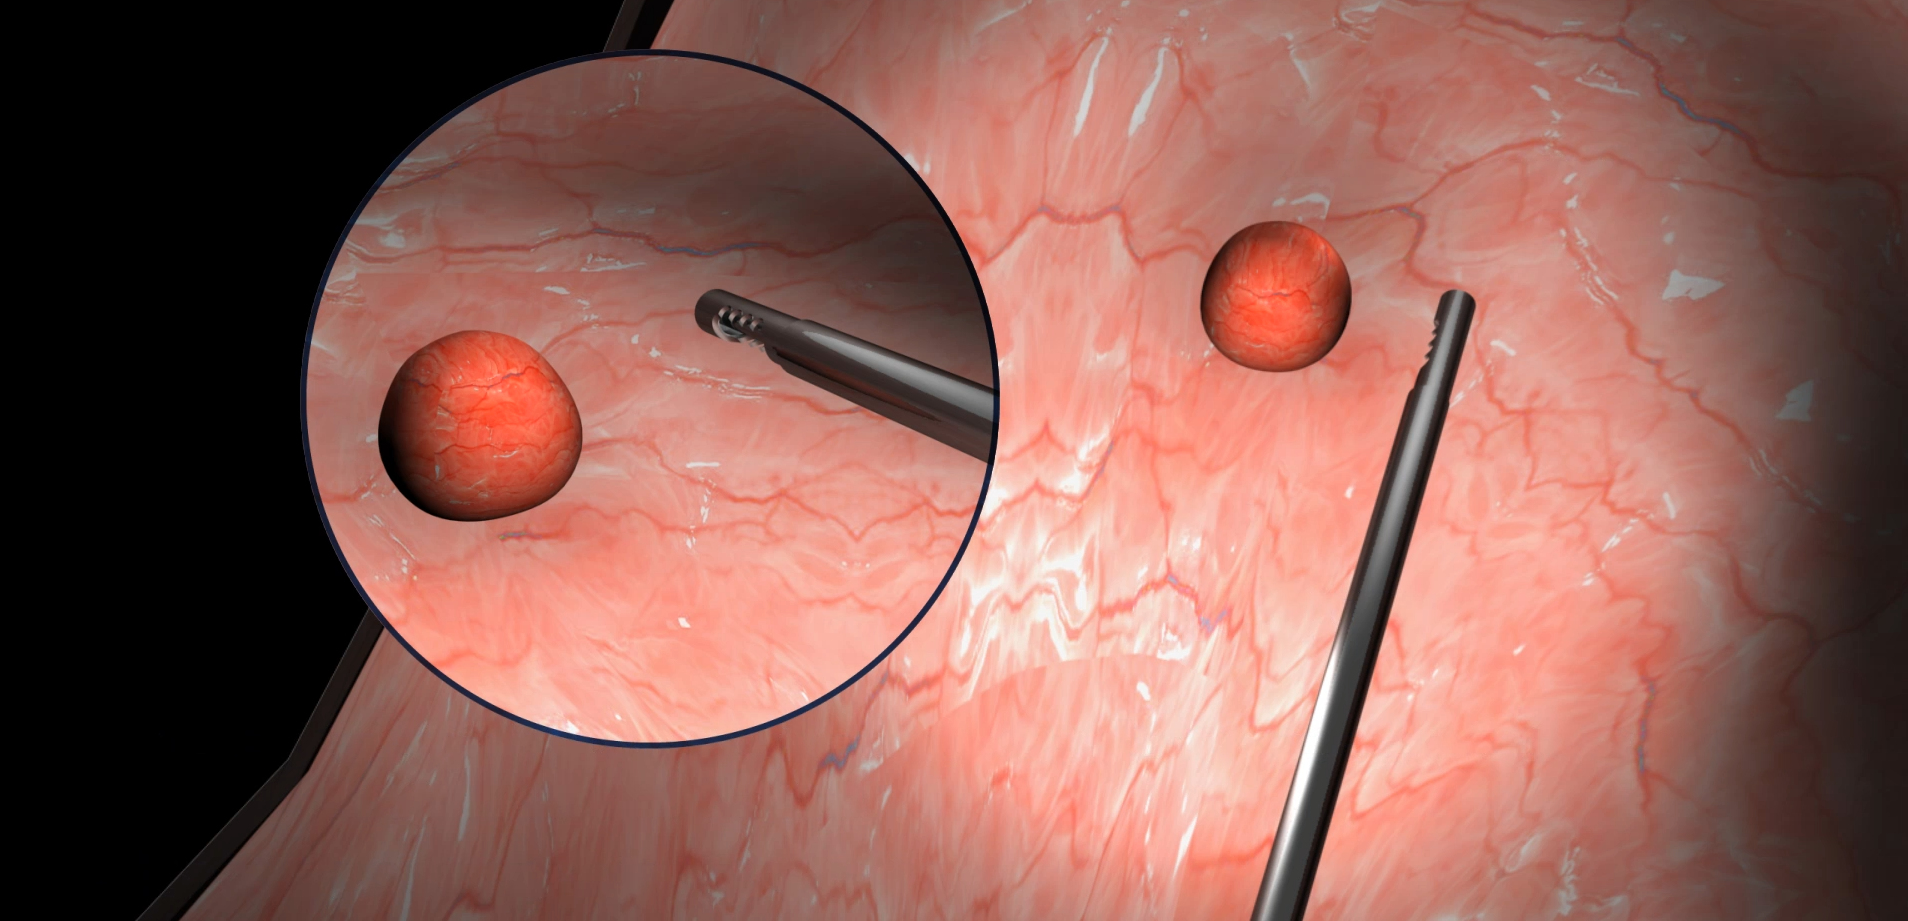

SHAVR

Tissue and/or pathology resection may be performed with a variety of surgical instruments, systems, and techniques including basic manual devices and electromechanical systems.

Basic manual devices are cost-effective and easy-to-use, but often lack speed, power, control, and effectiveness. Electromechanical systems may improve speed and power for certain cases, but require costly capital equipment, service contracts, complex set-up, and expensive disposables. Some electromechanical systems reduce physician tactile “feel” for the procedure and may introduce new risks that outweigh their benefit.

The SHAVR is a single-use, non-powered, hand-held, and hand-manipulated tool designed to combine the benefits of basic manual devices and electromechanically powered systems.

Clinicians squeeze and release the handle with their fingers to actuate cutting speed and control. Aspiration may be provided by wall suction and/or an aspiration pump. Improved control means physicians can perform surgical resection based on what they see and feel during the procedure.

INDICATIONS FOR USE: The Shavr is a non-powered, hand-held, and hand-manipulated manual surgical instrument for tissue resection. Shavr devices are “tools” not “treatments.”